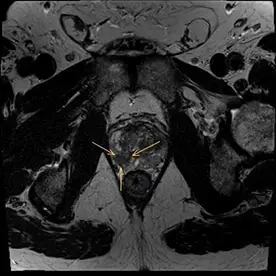

Es erfolgte eine multiparametrische MRT der Prostata mit intravenöser Kontrastmittelgabe. Neben einer Prostatahyperplasie mit ca. 47 ml Volumen zeigte sich der Nachweis von 2 malignitätssuspekten Läsionen.

Die Läsion 2 liegt in der peripheren Zone rechts apikal mit ebenfalls niedrigem Signal in T2w (Bild 3), Diffusionsstörung (Bild 4) und Korrelat in der DCE. Diese Läsion zeigt einen Kontakt zur Kapsel. Das neurovaskuläre Bündel wird hier ebenfalls nicht infiltriert. Die Läsion wurde als PI-RADS 4 klassifiziert und zeigt damit ein hohes Malignitätsrisiko.